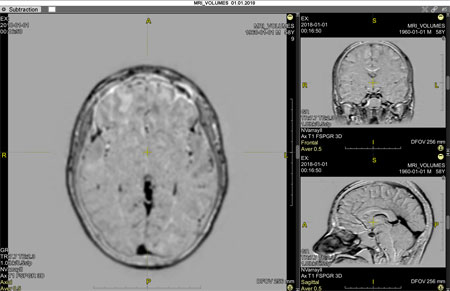

Click the OK button to enter Subtraction mode: